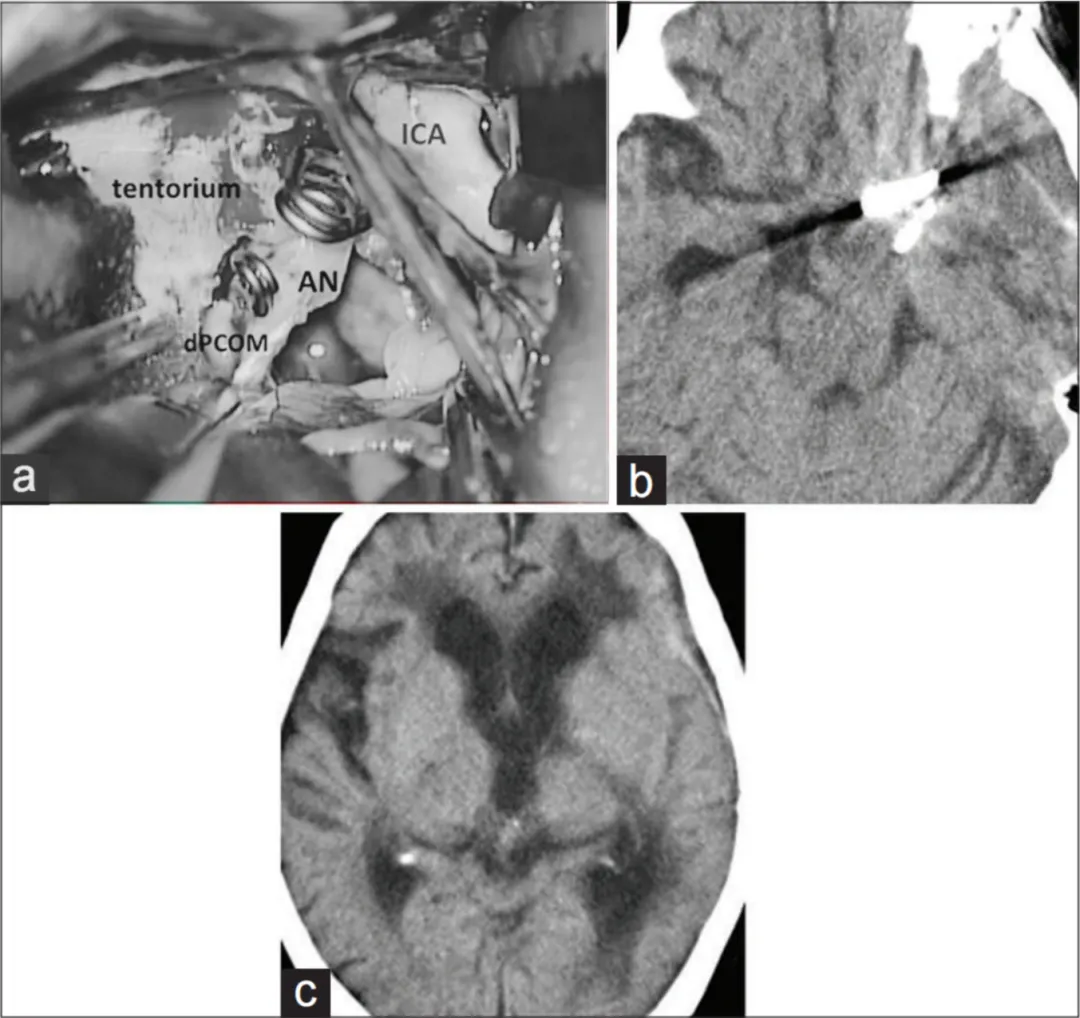

术前3D-CTA评估发现关键解剖特征:瘤体未见重要穿支血管发出,推测血栓形成已封闭血管开口,大脑后动脉可能建立代偿供血通路。基于此发现,手术团队决定实施动脉瘤夹闭孤立术联合血栓切除术。

手术过程与术后康复

采用左侧经外侧裂入路,在显微镜下完成动脉瘤夹闭操作,继行瘤体内血栓清除术。术中发现动脉瘤周围无重要滋养血管,脑干压迫得到有效解除。术后影像学检查确认无新发缺血病灶,脑干形态恢复良好。

患者神经功能显著改善,格拉斯哥昏迷评分恢复至15分,右侧肢体肌力提升至5级水平。术后一个月随访显示患者可在辅助下完成行走和进食活动,生活自理能力明显恢复。